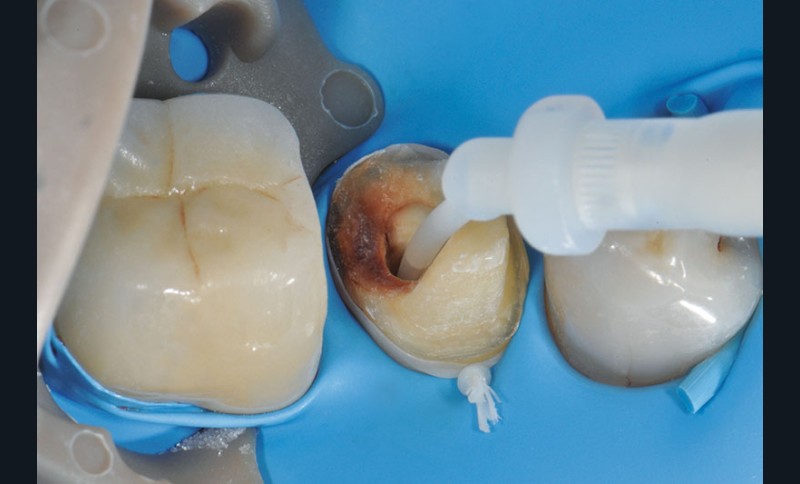

3, 4, 5. La restauration est déposée, les tissus carieux éliminés et la cavité d’accès aménagée avant la réalisation du traitement endodontique. La radiographie postopératoire permet de visualiser l’obturation du canal latéral en regard de la LIPOE.